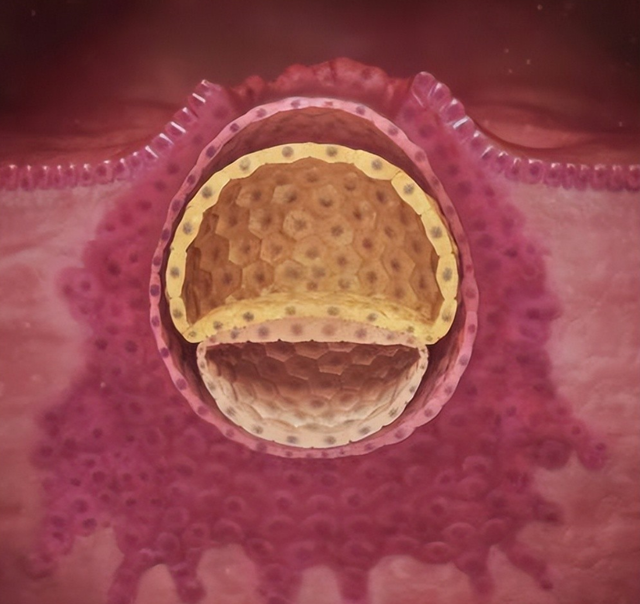

孕2~3周:胚胎植入

受精之后会陆续地分歧,然后滚到子宫找个地点着床。这技术有些姆妈可能会有轻细的出血,便是着床出血,有些姆妈可能会合计肚子有极少点疼。

孕4周:胚盘和体蒂

到了第4周,胚胎还只须胚盘和体蒂。